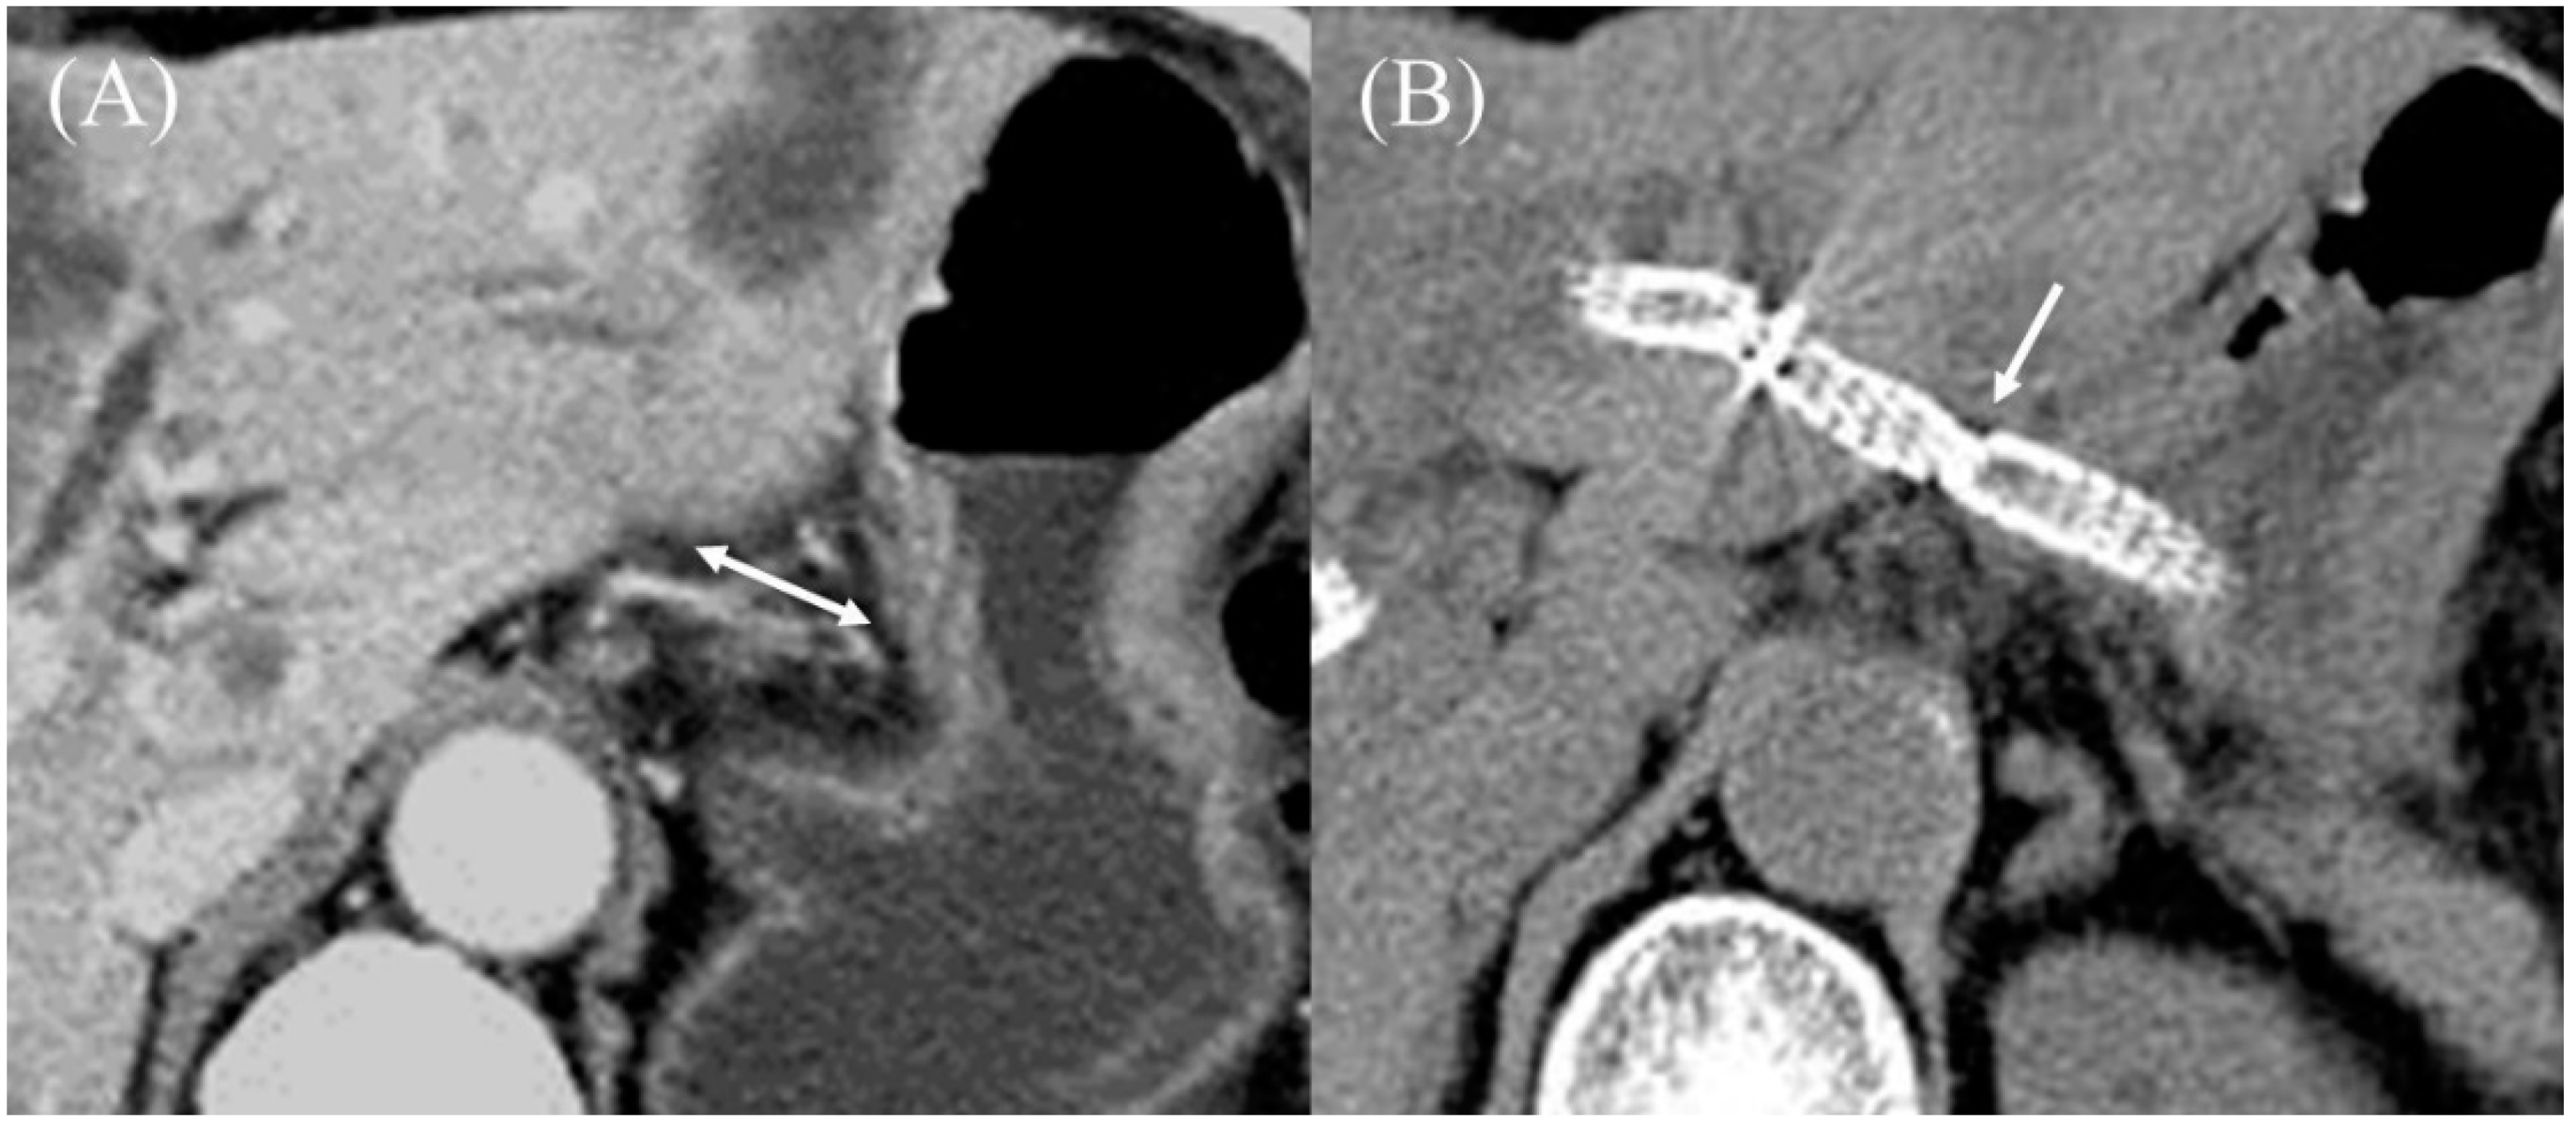

5.6. Stent Deployment